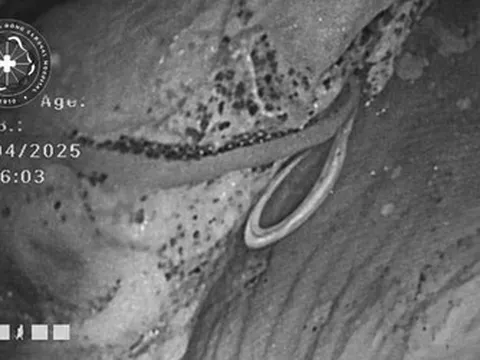

Và mới đây, một trường hợp tương tự tiếp tục được ghi nhận, gióng lên hồi chuông cảnh báo. Như đã đề cập, bệnh nhi đến khám tại Vũ Hán với biểu hiện nhìn mờ kéo dài. Kết quả kiểm tra cho thấy cả hai mắt đều nhiễm ấu trùng giun tròn Toxocariasis, gây tổn thương nghiêm trọng đến thị lực.

Qua thăm khám chuyên sâu, bác sĩ chẩn đoán bệnh nhi bị thoái hóa điểm vàng ở mắt phải và bệnh võng mạc trung tâm thanh dịch ở cả hai mắt. Đáng chú ý, cả hai mắt đều phát hiện nhiễm ấu trùng giun tròn Toxocariasis.

Sau khi xâm nhập qua đường tiêu hóa, trứng giun nở thành ấu trùng, xuyên qua thành ruột và theo đường máu di chuyển khắp cơ thể. Trong một số trường hợp, chúng có thể xâm nhập vào nhãn cầu, gây phản ứng viêm và tổn thương mô nghiêm trọng.

Khi ấu trùng xâm nhập sâu vào võng mạc, chúng có thể gây ra hàng loạt biến chứng như viêm nội nhãn, tổn thương võng mạc hoặc đục thủy tinh thể. Trường hợp nặng có thể dẫn đến teo nhãn cầu, thậm chí mù lòa.